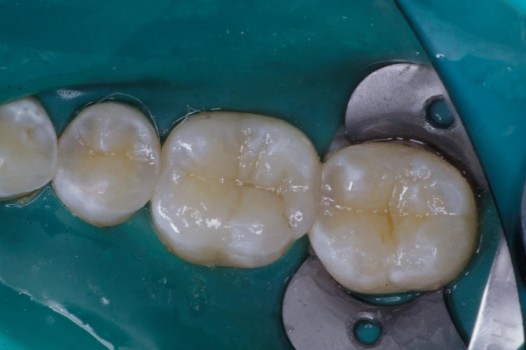

Using a modern diagnostic tool called Diagnodent, Dr. Klim can detect cavities before they become visible on an x-ray or to the naked eye. This allows him to repair tooth decay without a drill.

The pits and grooves on the biting surface of teeth often serve as plaque traps and pathways for bacteria to invade the inside of a tooth. This, in turn, leads to the development of cavities. Early diagnosis and treatment arrests the spread of decay and thus prolongs the life of the tooth. Regardless of the size of the affected tooth structure, decay may be swept away with the air abrasion technique and corrected by bonded ceramics, which seal the tooth against further bacterial invasion.